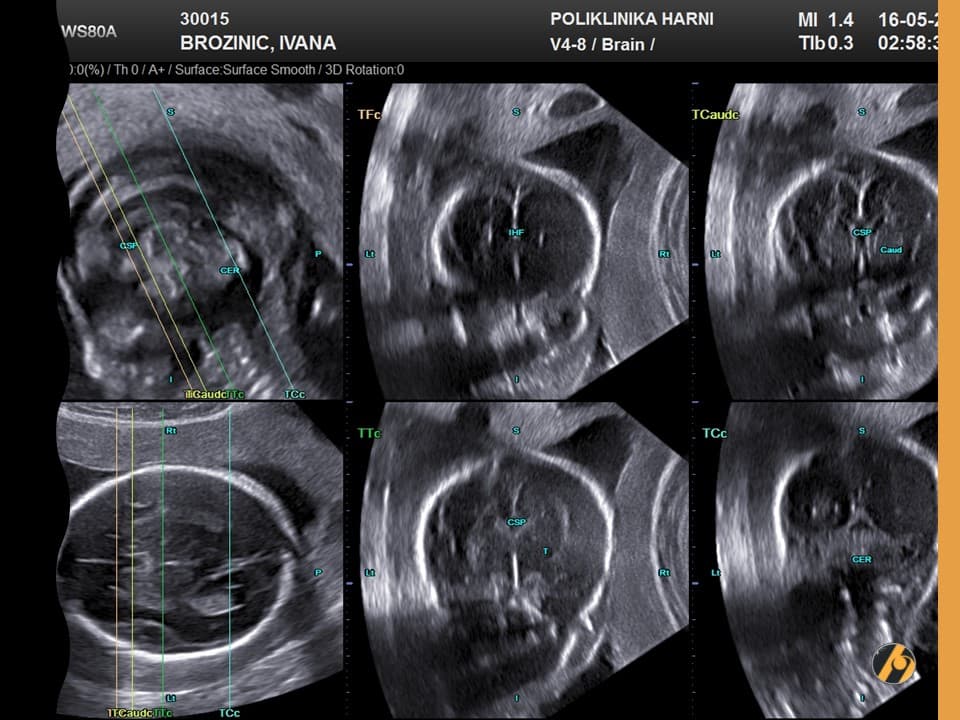

Najkasnije u 32. tjednu uredne trudnoće, planira se napraviti treći obavezni ultrazvučni pregled. Na ovom pregledu promatraju se položaj djeteta, položaj i izgled posteljice, te količina plodne vode. Ukoliko postoje nepravilnosti, ultrazvučni pregled će se ponoviti u kraćem vremenskom periodu. Osim položaja bebe i posteljice, uobičajeno vrše se standardna mjerenja i procjena rasta djeteta.

Sigurno ste već uočili u Vašoj ultrazvučnoj knjižici kratice tipa BPD, BIP, OFD, HC, THQ, AC, FL. Ovim kraticama obilježavaju se odgovarajući promjeri bebine glave, trbuha i bedrene kosti koji se uspoređuju s zadanim krivuljama i tablicama.